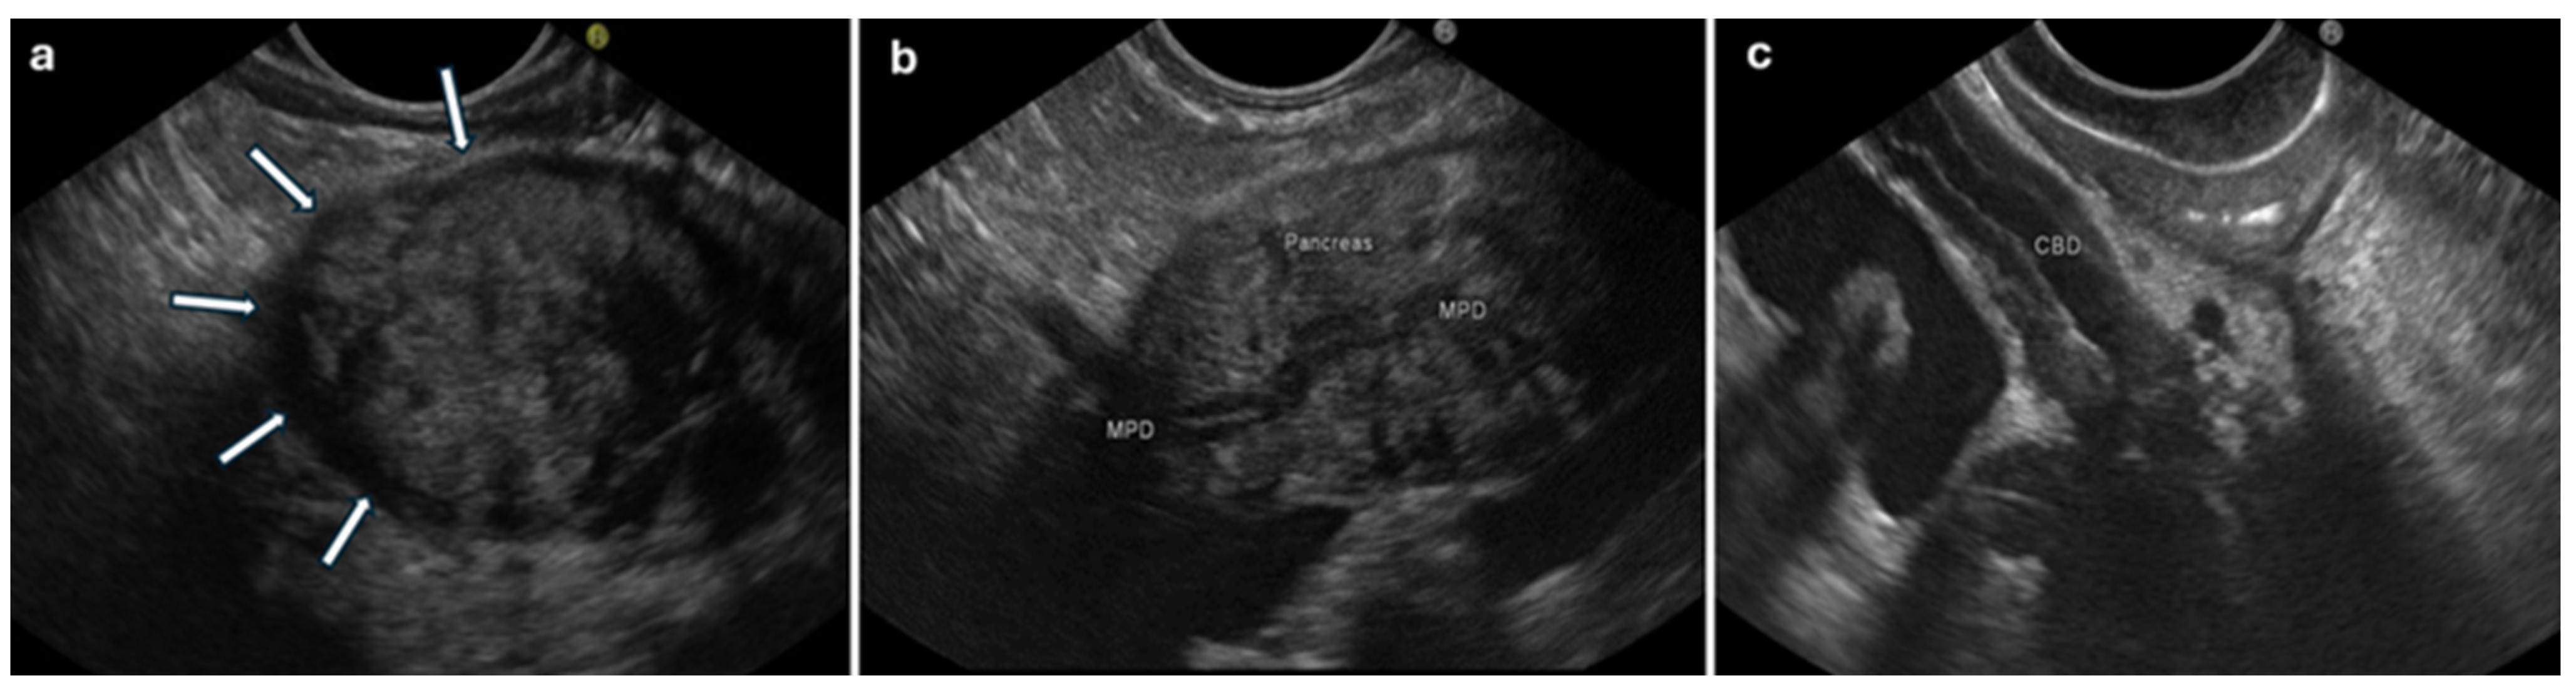

- Hoki, N.; Mizuno, N.; Sawaki, A.; Tajika, M.; Takayama, R.; Shimizu, Y.; Bhatia, V.; Yamao, K. Diagnosis of autoimmune pancreatitis using endoscopic ultrasonography. J. Gastroenterol. 2009, 44, 154–159. [Google Scholar] [CrossRef] [PubMed]

- Buscarini, E.; De Lisi, S.; Arcidiacono, P.G.; Petrone, M.C.; Fuini, A.; Conigliaro, R.; Manfredi, G.; Manta, R.; Reggio, D.; De Angelis, C. Endoscopic ultrasonography findings in autoimmune pancreatitis. World J. Gastroenterol. 2011, 17, 2080–2085. [Google Scholar] [CrossRef] [PubMed]

- Zhang, S.-Y.; Feng, Y.-L.; Zou, L.; Wu, X.; Guo, T.; Jiang, Q.-W.; Wang, Q.; Lai, Y.-M.; Tang, S.-J.; Yang, A.-M. Endoscopic ultrasound features of autoimmune pancreatitis: The typical findings and chronic pancreatitis changes. World J. Gastroenterol. 2021, 27, 7376–7386. [Google Scholar] [CrossRef] [PubMed]

- Farrell, J.J.; Garber, J.; Sahani, D.; Brugge, W.R. EUS findings in patients with autoimmune pancreatitis. Gastrointest. Endosc. 2004, 60, 927–936. [Google Scholar] [CrossRef] [PubMed]

- Yang, A.; Guo, T.; Xu, T.; Zhang, S.; Lai, Y.; Wu, X.; Wu, D.; Feng, Y.; Jiang, Q.; Wang, Q.; et al. The role of EUS in diagnosing focal autoimmune pancreatitis and differentiating it from pancreatic cancer. Endosc. Ultrasound 2021, 10, 280–287. [Google Scholar] [CrossRef] [PubMed]

| Gland volume: diffuse enlargement | Gland volume: focal enlargement (within the pancreatic head in about 2/3 of cases) [37] | Caliber: dilated. | Wall: thickened. | Volume: enlarged (≥8 mm) [48] | The loss of interface between the pancreas and vessels of the portal system and potentially others [48] |

| Echotexture: diffuse hypoechogenicity, diffuse hypoechoic areas | Echotexture: focal or diffuse hypoechogenicity [48] | Wall: regular homogenous thickening typically with a hyper–hypo–hyperechoic series of layers (“sandwich pattern”) or parenchymal echo type [62] | Echotexture: hypoechoic | ||

| Parenchymal heterogeneity: hyperechoic foci, lobularity †,∆, hyperechoic strands ∆ | |||||

| MPD: hyperechoic margin [1], irregular narrowing | MPD: hyperechoic margin [1], irregular narrowing, upstream dilation [37,48] | ||||

| Peripancreatic changes: peripancreatic hypoechoic margin [37], lobular outer margin ∆ | Peripancreatic changes: lobular outer margin ∆ [37,47] | ||||

| Conventional EUS | Diffuse hypoechogenicity Diffuse or focal hypoechoic areas Hyperechoic foci/strands Lobularity Peripancreatic hypoechoic margin Duct-penetrating sign † Hyperechoic MPD margin Irregular MPD narrowing ∆ Bile duct wall thickening ° Lymphadenopathy ^ | Focal hypoechogenicity MPD dilation Vascular invasion |